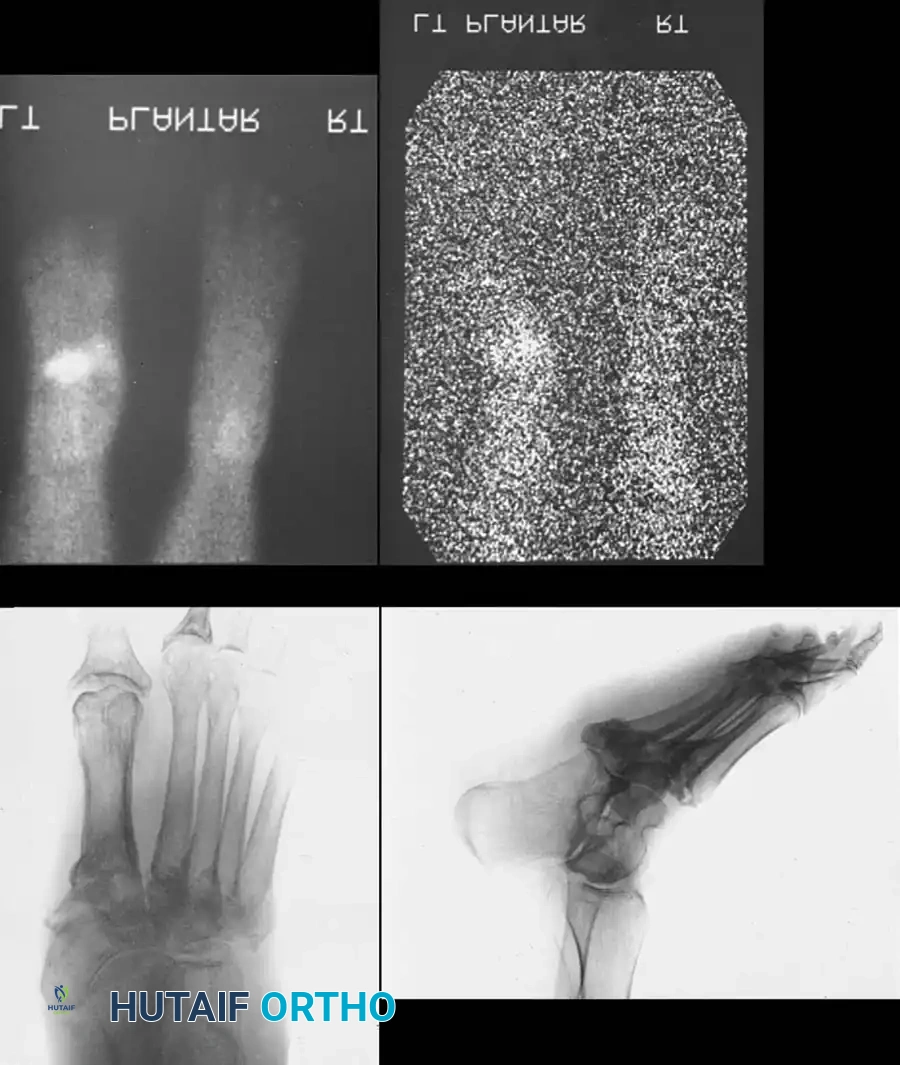

In the early stages, routine radiographs may appear entirely normal. A technetium-99m bone scan or MRI is highly sensitive and will be positive before radiographic destruction is visible. Indium-111 labeled white blood cell scans may be required to differentiate acute Charcot from osteomyelitis.

FIXED DEFORMITIES IN THE DIABETIC FOOT Surgical Diagram

Associated Surgical & Radiographic Imaging

Hutaifortho's Orthopaedic Diagram